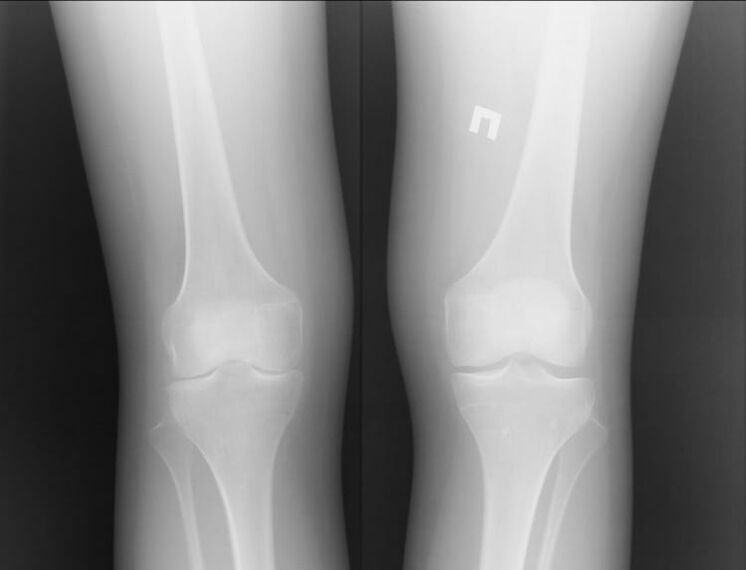

Por suposto, ambas as dúas enfermidades son bastante graves e é difícil dicir cal é peor. Non obstante, podemos considerar o exemplo dun problema na articulación do xeonllo. Con artrite, é dicir, con procesos inflamatorios, pódese axudar ao paciente.

Na maioría das veces isto ocorre debido a outras infeccións que se producen no corpo humano. Se están curados e elimínase a inflamación da articulación, entón a artrite do xeonllo xa non che molestará.

A artrose é unha historia completamente diferente. Esta é unha enfermidade independente causada por problemas no tecido da cartilaxe. Moitas veces isto non se pode facer sen intervención cirúrxica. A isto séguelle outro longo proceso de recuperación.

Polo tanto, podemos dicir que a artrose é unha enfermidade máis grave. Non obstante, a artrite pode causar a primeira enfermidade. Ambas as enfermidades non deben ser descoidadas. É mellor contactar inmediatamente cun especialista.